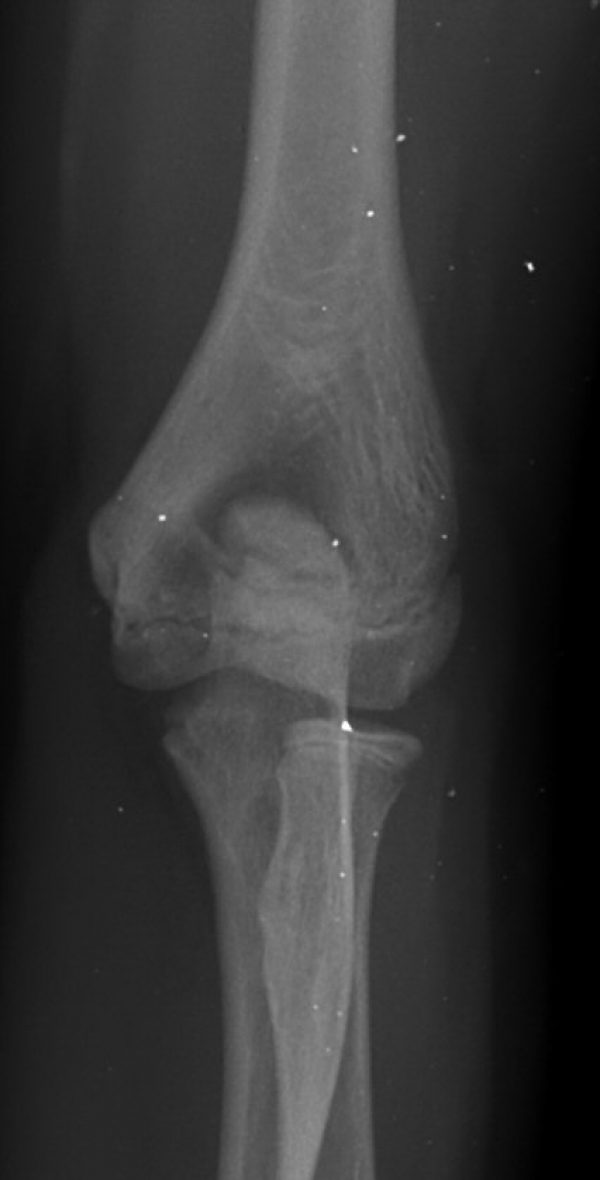

ÆÈ²ÞÄ¡ ³»»ó°ú ¿ÜÃø¿¡ ¹Ì¼¼ÇÑ °ñÆíÀÌ °üÂû µÊ(±×¸² 7).

ÆÈ²ÞÄ¡ ̫̿ ÃøºÎÀÎ´ë ÆÄ¿­ ¹× °ß¿­°ñÀý(±×¸² 8, 9)